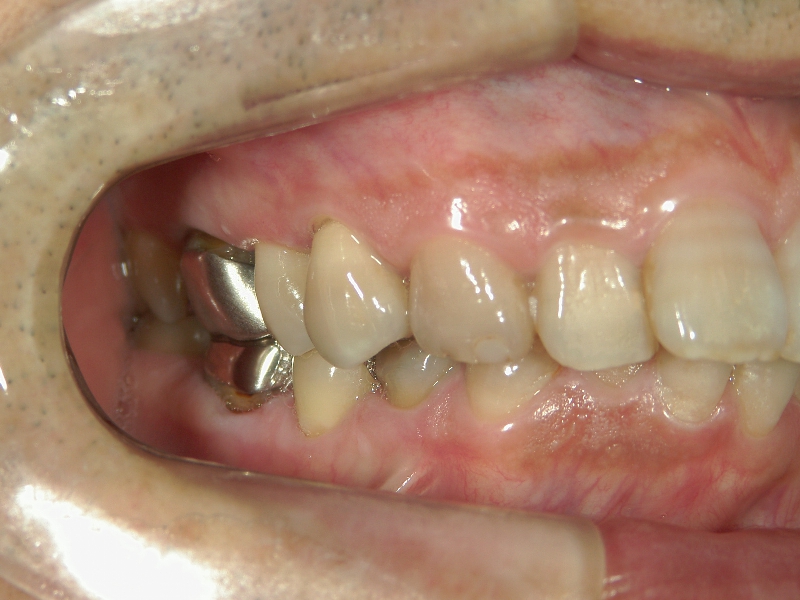

矯正歯科 治療後矯正歯科 全顎ワイヤー矯正 治療後矯正歯科(全顎ワイヤー矯正)治療後

矯正歯科 治療後 左上6番欠損のため、7番を6番の位置へ前方牽引

no.22_8175_治療後_右.jpgno.22_8175_治療後_正面.jpgno.22_8175_治療後_左.jpg